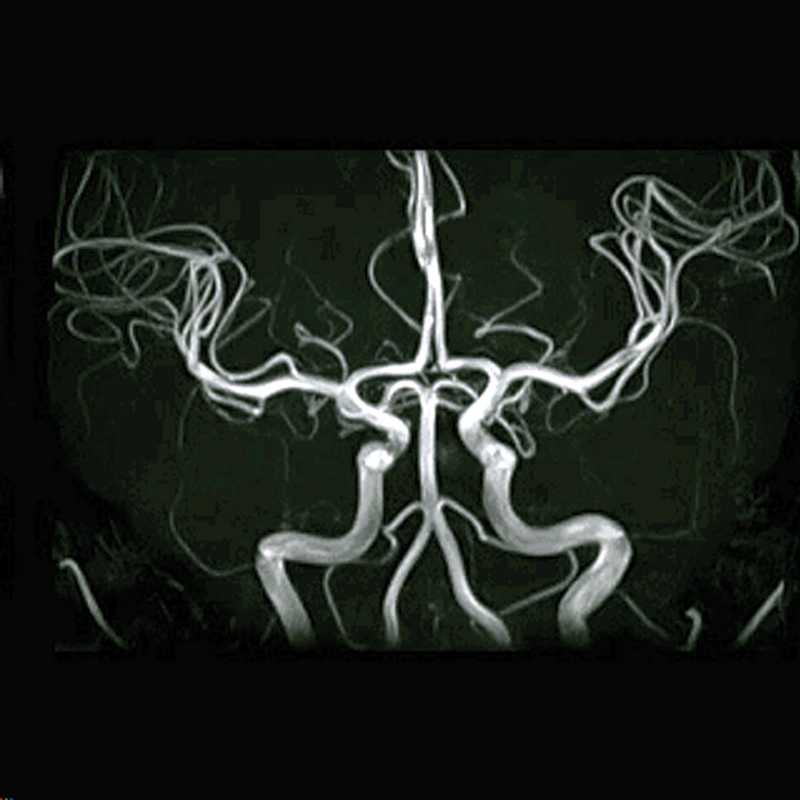

º£Æü¤Ï¼ó¼þ¤ê¤Î¥¨¥³¡¼´Æºº¤È

¼ó¤ÈƬ¤ÎMRI¤ÈMRA¸¡ºº¡£

¤½¤¦¸À¤¨¤ÐMRA¤È¸À¤¦¤Î¤¬½é¤á¤Æ¤À¤Ã¤¿¡£

MRI¤ÏÃÇÌÌÎØÀÚ¤ê¤ÇÄ´¤Ù¤ëÊýË¡¡£

MRA¤Ï·ì´É¤ò£³D¾õÂÖ¤ÇÄ´¤Ù¤ë¤È¸À¤¦¡£

±ÇÁü¤ò¸«¤¿¤¬¡¢·ì´É¤À¤±¤¬Î©ÂÎŪ¤Ë¸«¤¨¤ë¡£